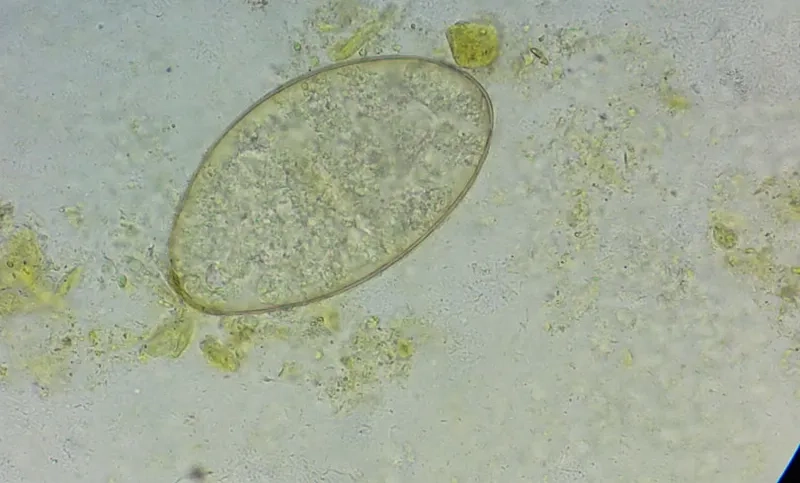

Image of the disease Fascioliasis